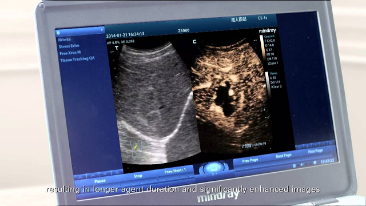

Single Crystal ile 3T Prob Teknolojisi Tek Kristalli

Daha belirgin g?rĂŒntĂŒler sa?layan, M9 ile uyumlu tĂŒm problar Mindray'in benzersiz 3T prob teknolojisiyle teslim edilir. Single crystal teknolojisinin eklenmesiyle gĂŒcĂŒ artan M9, ?zellikle zorlu hasta taramas? s?ras?nda daha iyi penetrasyon ve dinamik renk ak??? olana?? sunar.